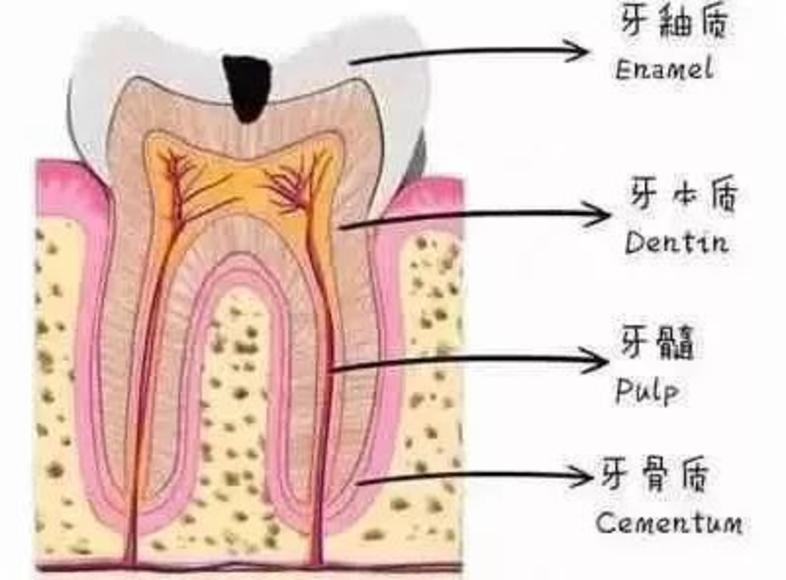

牙齿分为三层,最外层坚硬的牙釉质,不会感觉到疼痛;中间的牙本质能够感受到疼痛;最里层是敏感的牙神经,一受刺激便会疼痛难忍。

浅龋齿:细菌到达牙釉质层,患者没有明显感觉

中龋齿:细菌到达牙本质,一开始会感觉酸痛,一段时间后酸痛感就会消失

深层龋齿:细菌到达牙本质深层,接近牙髓,咬东西时会感到刺痛,疼痛感会反复出现.

牙髓炎:细菌进入牙神经,患者会有剧烈的疼痛感。如果不及时治疗,细菌会杀死牙神经

运气好的话牙齿里面是这样的↓↓